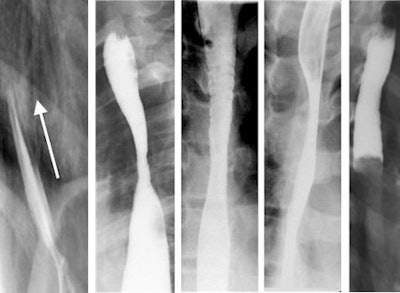

| Single-contrast esophagrams in five different patients with eosinophilic esophagitis show the different findings of this disorder. Left to right: gastroesophageal reflux, midesophageal stricture, a ringed esophagus, dysmotility, and an impacted food bolus. Image courtesy of Dr. Alexander Towbin, Cincinnati Children's Hospital Medical Center. |

Twenty percent of the patients had gastroesophageal reflux, and 14% had irregular contractions. Eleven patients were diagnosed with strictures, three in the midesophagus and eight in the distal esophagus. Nine patients were identified with dysmotility, seven with mucosal irregularities, six with rings, and three with filling defects.

Seventy-one patients, or 53% of the total, were normal. Diniz attributed the lack of imaging findings to deep infiltration, mild inflammation, or mucosal findings that could not be identified on a single contrast study.

The study found that the utility of esophagrams was limited in this patient population. Although approximately 50% of the patients had at least one esophageal finding at fluoroscopy, no one finding occurred with enough frequency to reliably suggest a diagnosis, they said.